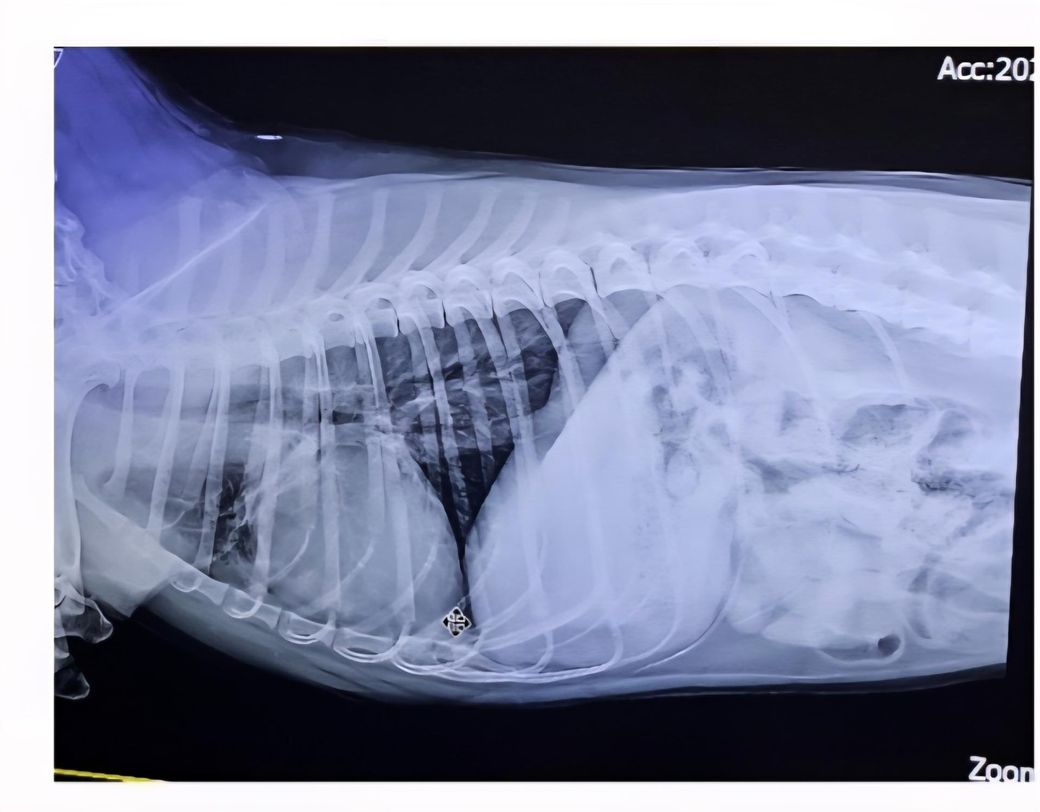

며칠전부터 간헐적으로 켁켁거리고 어제밤에는 빈도가 잦아지고 그르렁소리까지 나는듯하여 병원에 내원했습니다. 가벼운 기관지염이라고 약을 받아 왔는데 폐나 심장은 괜찮은건지 판독 부탁드립니다.

원본 사진이 아니면 판단의 정확도가 낮아 오진의 가능성이 높기 때문에 판독 불가합니다. 원본 이미지를 보고 판단하는 주치의의 의견을 신뢰하기기 바랍니다. 가장 정확한 소견입니다.